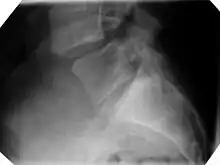

X-ray picture of a grade 1 isthmic anterolisthesis at L4-5 -

Plain radiography is often the first step in medical imaging.[13] Anteroposterior (front-back) and lateral (side) images are used to allow the physician to view the spine at multiple angles.[13] Oblique view are no longer recommended.[24][25] In evaluating for spondylolithesis, plain radiographs provide information on the positioning and structural integrity of the spine. Therefore, if further detail is needed a physician may request advanced imaging.